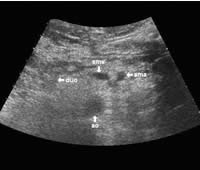

The following study describes anatomical landmarks in the ordinary pancreas of a thin patient:

Transverse planes in caudal direction: